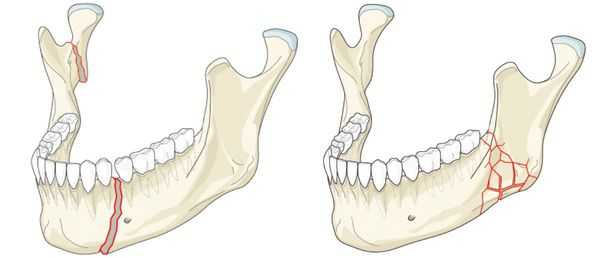

Перелом нижней челюсти — это нарушение целостности кости в одном или нескольких отделах.

Наиболее частой причиной возникновения перелома нижней челюсти является травматический фактор. В ряде случаев речь может идти о патологическом переломе из-за деструктивных процессов в костной ткани. [1] К таким патологическим процессам относятся:

Развиваются при повреждении фактором, который по силе или интенсивности воздействия превышает упругие и прочностные свойства кости. Линия перелома возникает в месте ее пониженной плотности, что является “благоприятным” условием для развития перелома [14,19].

Причиной может быть удар в область нижней челюсти, падение с высоты, компрессия (сдавление) челюсти, ее сотрясение, огнестрельное ранение. Воздействие механического фактора приводит к нарушению целостности кости и ее перелому [7].

Травматическим повреждениям в большей степени подвержен подбородок, углы нижней челюсти и суставные отростки (мыщелковый, венечный).